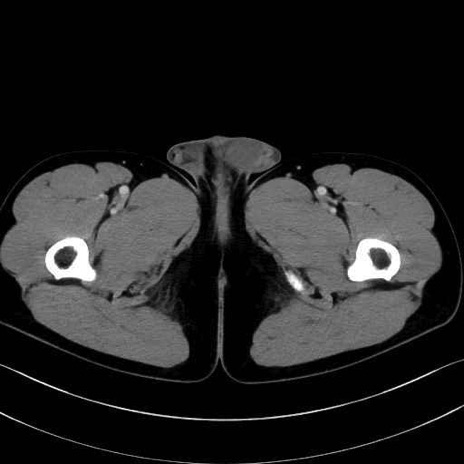

内閉鎖筋 (Obturator internus)

外閉鎖筋 (Obturator externus)